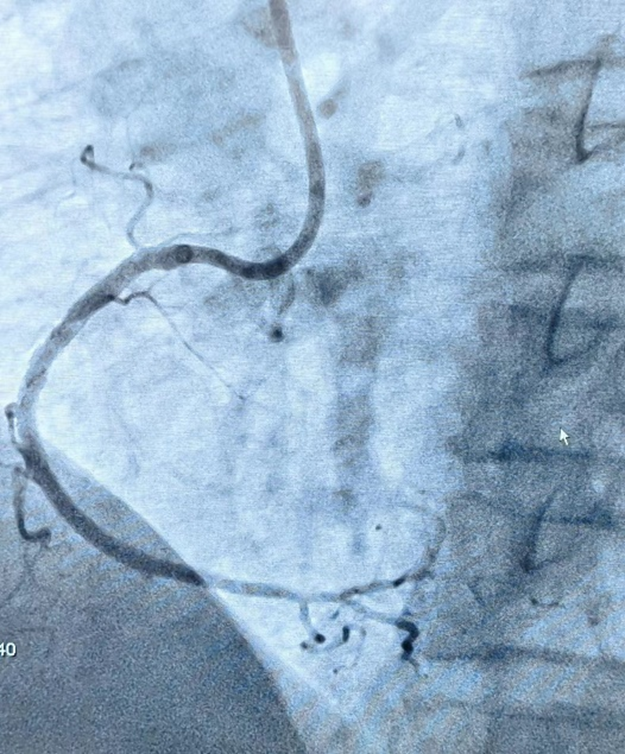

术前李逢春主任与杨征医生团队仔细阅片,综合评估患者术中经判读冠脉造影提示右冠 1 段完全闭塞,远端可见桥血管及 LCX 提供侧枝逆灌。患者血管自身条件非常差,存在多支病变;CTO 段逆向供血血管环境极差,全程弥漫性病变、严重狭窄伴溃疡。正向逆向均无明显入路,这给术者带来了极大的挑战。

杨征团队尝试正向进入闭塞段,但因其病变部位复杂,导丝触觉反馈提示 CTO 帽钙化严重,立即果断改用逆向开通。但又出现了一个致命性问题,经过冠脉造影发现:因其侧枝循环的特殊性,与回旋支连接,未与间隔支相连。要想通过侧枝循环进入闭塞的右冠远端,就必须通过位于心外膜的侧枝循环进入。因患者逆向血管严重扭曲、纤细,通过风险极高,位于心外膜侧枝血管一旦操作不当,极易发生右冠远端血流消失,供血心肌面梗死,或导致穿孔心包填塞发生。所以此项操作要求术者必须有高超的技术。经过以毫米为单位的精密手法,杨征手术团队通过微导管的支撑下,反复升级、降级导丝,从迷失方向到柳暗花明,最终顺利通过扭曲极其严重的侧枝循环到达右冠远端。

对于钙化、扭曲、血管走形不清的 CTO 血管段,反复尝试且逐步升级逆向导丝均不能通过闭塞段,为提高 CTO 段开通效率,术者巧妙使用导丝行 Knuckle 技术,通过推进 J 形结构的亲水导丝在内膜下空间进行钝性剥离,为下一步行 CART 技术提供支持。

通过严重迂曲心外膜通道的逆向导丝有了逆向导丝指引,术者再次尝试正向进入靶病变,应用 CART 技术,通过手感对斑块软硬程度的认知,经过延长导管与微导管配合,正向反复尝试、升级导丝,最终使用导丝正向通过夹层通路。正向导丝与逆向导丝慢慢会师,双向导丝交汇,多体位证实导丝无限接近。继续操作正向导丝缓慢前行,顺利进入逆向微导管内,并送入 AV 支。

正向导丝进入逆向微导管经过 IVUS 观察,近端纤维帽提示 360 度环形钙化,应用预扩球囊、切割球囊及非顺应性球囊处理后,顺利植入支架,复查 IVUS 提示支架膨胀贴壁良好,无血肿、夹层形成,血流 TIMI 3 级。